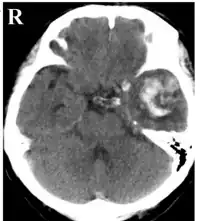

CT showing a cerebral contusion (and ICH) in the left temporal region